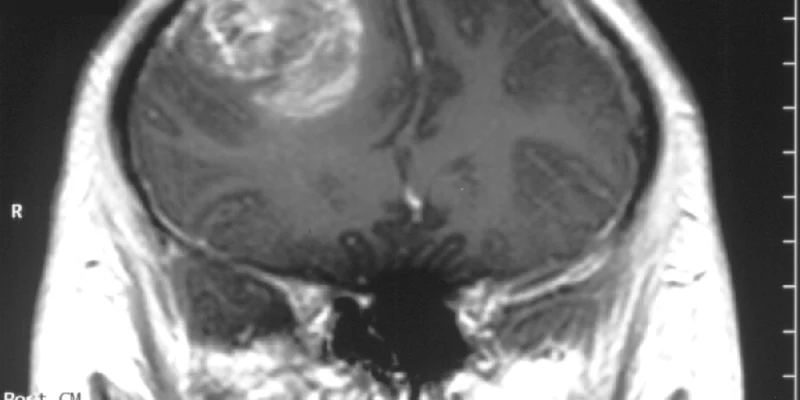

Kanados mokslininkai atrado netikėtą glioblastomos, vienos iš pavojingiausių smegenų vėžio formų, silpnybę. Tyrimo metu nustatyta, kad tam tikros smegenų ląstelės, anksčiau laikytos tik normalios nervų funkcijos palaikytojomis, gali iš tikrųjų padėti navikams augti, siųsdamos signalus, kurie stiprina vėžio ląsteles. Blokuojant šią komunikaciją laboratoriniais modeliais, naviko augimas dramatiškai sulėtėjo.

Mokslininkai ilgą laiką žinojo, kad glioblastomos augimui reikalingi tarpusavyje bendraujančių ląstelių tinklai. Šio tyrimo tikslas buvo nustatyti, kurios konkrečios smegenų ląstelės dalyvauja šiame procese. Tyrėjai nustatė, kad oligodendrocitai, kurie paprastai saugo nervų skaidulas, gali pakeisti savo elgesį ir pradėti palaikyti navikų augimą. Šios ląstelės bendrauja su vėžio ląstelėmis per aiškiai apibrėžtą signalizacijos sistemą, kuri sukuria sąlygas, leidžiančias navikui išgyventi ir plėstis. Kai ši signalizacija buvo blokuota laboratoriniuose modeliuose, naviko augimas žymiai sulėtėjo, parodydamas, kiek svarbi yra ši sąveika.